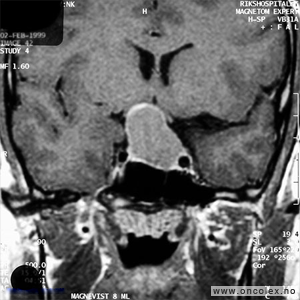

Knosp klassifikasjon brukes for å beskrive svulstenes utbredelse fra midtlinjen og ut til sidene. Klassifikasjonen deler svulstene inn i grad fra 0 til 4, hvor grad 0 er svulster i hypofysegropen uten utbredelse inn i sinus cavernosus, og grad 4 er svulster som omslutter den indre halsarterien (arteria carotis interna). Grad 4 svulster og svulster som brer seg ut til siden for den indre halsarterien (Knosp grad 3) er svært vanskelig å fjerne fullstendig med operasjon.

Bildeserie av stadieinndeling av hypofysesvulster (Knosp klassifikasjon)